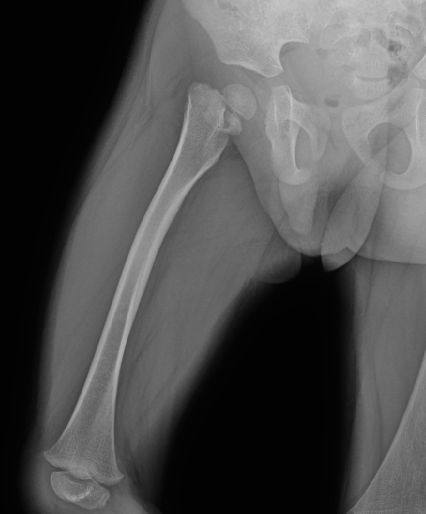

影像资料:

骨盆正位